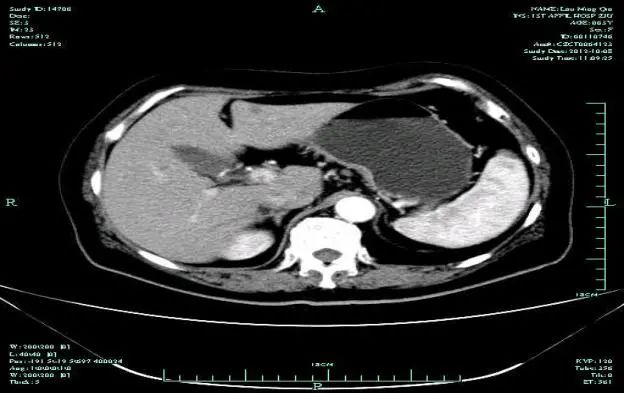

CT-T

CT-H1

MR-H1

影像学检查结果评估:cPD。